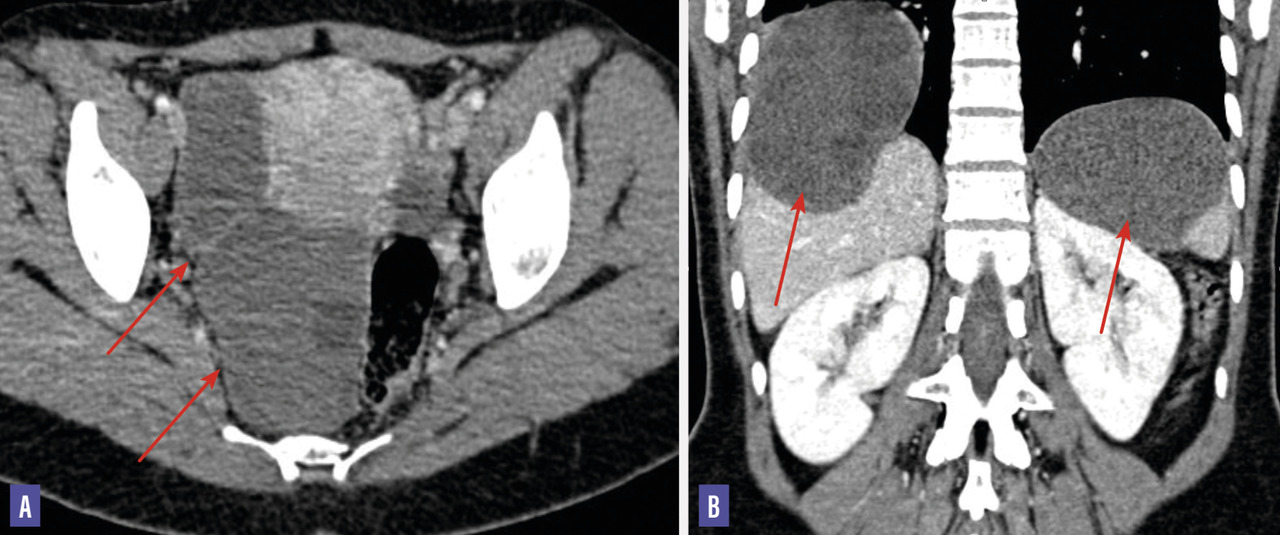

Une patiente âgée de 44 ans, opérée pour un kyste hydatique hépatique seize ans auparavant, consulte pour des douleurs abdomino-pelviennes intermittentes et une irrégularité du cycle menstruel. L‘examen clinique révèle une masse annexielle droite, sensible et indépendante de l’utérus ainsi qu’une hépatosplénomégalie. L’état général est conservé. L’hémogramme montre une hyperleucocytose à 24 800/mm3 à prédominance de neutrophiles et une anémie hypochrome microcytaire. La sérologie hydatique est positive. L’échographie pelvienne met en évidence deux formations en régions ovarienne et rétro-utérine droites, bien limitées, renfermant plusieurs structures serpigineuses rappelant des membranes proligères, et des images multi­vésiculaires, mesurant 42 × 40 mm et 80 × 73 mm. Ces observations permettent d’évoquer le diagnostic de kyste hydatique ovarien organique classé type III de la classification de Gharbi. Le balayage hépatosplénique trouve des kystes hydatiques spléniques et hépatiques du segment IV classés type III de la classification de Gharbi. La tomodensitométrie (TDM) abdomino-pelvienne (fig. 1) confirme la présence de deux formations ovariennes et rétro-utérines droites ovalaires, mal limitées, à paroi fine, de densité liquidienne, qui renferment une membrane décollée avec une localisation hépatosplénique. L’imagerie par résonance magnétique (IRM) pelvienne (fig. 2 et 3) précise l’aspect des deux volumineuses masses : une latéro-utérine et l’autre rétro-utérine à droite, de contours réguliers, bien limitées, à paroi fine, de signal hétérogène T2, renfermant des vésicules filles en hypersignal T2 franc liquidien sans restriction de la diffusion et ne se rehaussant pas après injection. La patiente a bénéficié d’une intervention chirurgicale, qui a trouvé deux kystes pelviens latéro-utérins de 8 cm de diamètre pour le plus volumineux. L’étude anatomopathologique a confirmé le diagnostic de kyste hydatique.  Les suites postopératoires ont été simples, avec un traitement médical adjuvant par albendazole.